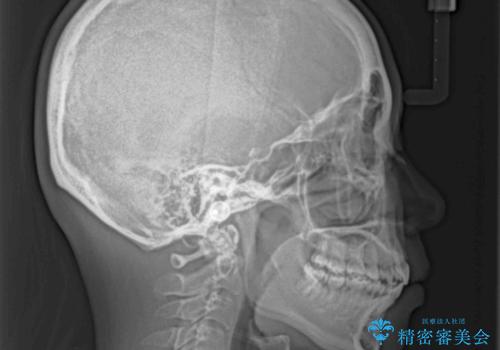

- 前歯のデコボコと口元の突出感を気にして来院された患者様です。

上下左右第一小臼歯4本を抜歯し、ワイヤー装置にて口元を引っ込めるよう矯正治療を行うこととしました。

叢生が強かったため、口元の突出感の改善には限界がありましたが、横側からも口元が引っ込んだ感じが分かるほど改善されました。